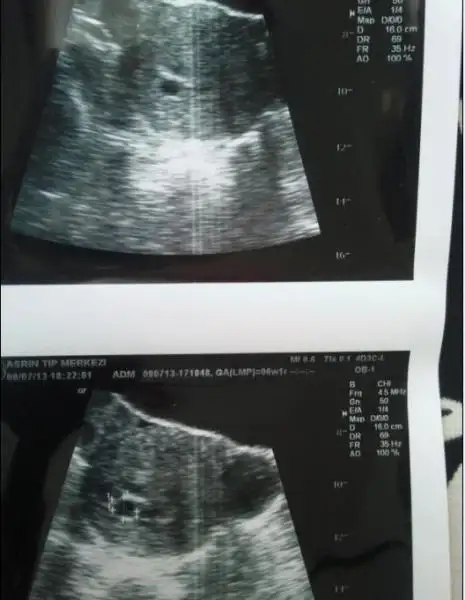

olur mu olur heee kan değerin kaçtı canım seninBu da miniğimizin ilk görüntüsü;

Eki Görüntüle 753753

Yalnız kesenin hemen sağındaki yine kese gibi duran karartıyı siz de farkettiniz mi? Eve geldiğimde farkettim onu. DOktor onunla ilgili bir şey de söylemedi ama ne bileyim, ikiz olmasın sonra![]()